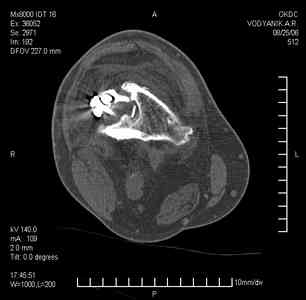

Тугой ложный сустав правого бедра в сочетании неправильно сросшимся переломом большеберцовой кости

В 2002 v внутрисуставной оскольчатый перелом проксимального метаэпифиза правой большеберцовой кости; в 2005 v внутрисуставной оскольчатый перелом дистального метаэпифиза правой бедренной кости.

В обоих случаях в разных лечебных учреждениях проводилось оперативное лечение переломов. При осмотре в отделении на основании результатов клинического осмотра и данных визуальных методов обследования поставлен диагноз: тугой ложный сустав дистальной трети правой бедренной кости, состояние после накостного остеосинтеза перелома типа 33-В2.2 ; несросшийся перелом надколенника; неправильно сросшийся перелом латерального мыщелка правой большеберцовой кости, состояние после металлоостеосинтеза перелома 41-В2.2; сочетанная осевая деформация правой ноги: варусная деформация правого бедра, вальгусная деформация правой голени; посттравматический артроз коленного сустава 4 ст по Kellgren-Lowrence; выраженное нарушение функции ходьбы и опоры.

Внешний вид ноги больного, данные рентгенографического обследования и избирательно выделенные компьютерные томограммы приведены в приложении. В именах КТ использовано кодирование уровня по АО, т.е. _41, например, означает проксимальную треть голени. В отделении намечен v очень предварительно v следующий план лечения: